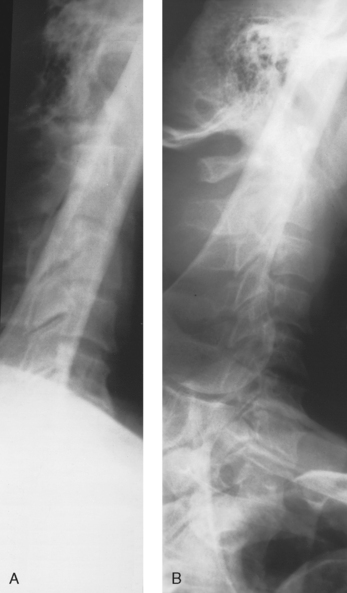

• The Ferlic swimmer’s filter is a collimator-mounted filter created to improve imaging of the lateral projection of the cervicothoracic region (swimmer’s technique) (Fig. 2-8), but it is also used for the axiolateral projection of the hip (Danelius-Miller method) (Fig. 2-9). The Ferlic shoulder filter, also a collimator-mounted filter, is designed specifically to image the shoulder in both the supine and upright positions.

Fig. 2-8 A, Lateral projection of cervicothoracic region (swimmer’s technique) without compensating filter. B, Same projection with Ferlic swimmer’s filter. Note how C7-T1 area is penetrated and shown.